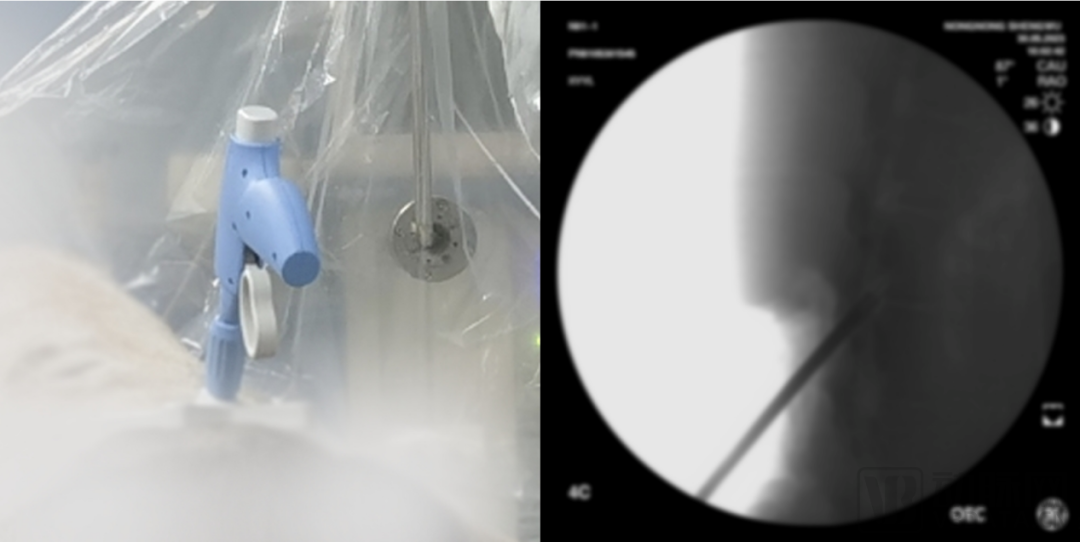

目前,新云医疗已搭建起覆盖微创手术、神经调控、经皮电刺激三大领域的疼痛产品管线,其中多款产品打破了国外企业的技术垄断。在覆盖疼痛患者多、手术量大的微创介入领域,新云医疗自主研发出国内首款针对腰椎管狭窄症(LSS)的微创手术器械套件NewMild,将为黄韧带肥厚型LSS提供更优术式。该微创手术仅需一个微小的切口即可切除多余韧带,从源头上治疗LSS,且具有类似于硬膜外类固醇注射的安全特性,患者通常在手术24小时后便可自由活动,在缩短患者康复期的同时也减轻其经济负担。

利用NewMild开展腰椎管狭窄症微创减压手术腰椎管狭窄患者广泛分布在基层,通过NewMild开展手术,可降低操作难度,缩短基层医生学习曲线,提高基层患者的治疗率。赵云提到,在患者自愿且条件允许的情况下,这类腰椎管狭窄症微创术式有望开展日间手术,缓解医院床位紧张的问题,整体的手术费用也会降低。在高壁垒的神经调控领域,新云医疗推出国内首款闭环有源植入可充电式脊髓电刺激系统。近年来,以脊髓电刺激(SCS)为代表的神经调控技术,在治疗慢性疼痛上表现出优异的效果,雅培、美敦力等国际巨头纷纷加大SCS研发投入。目前主流的脊髓电刺激系统是一种开环的刺激系统。术中,根据患者的感觉异常、疼痛缓解程度选择有效的刺激参数,确定后固定刺激参数。术后一段时间,需要通过远程控制改变刺激幅度,降低刺激过大或不足的可能性,但存在治疗效果减弱的风险。由于患者在呼吸、咳嗽、心跳和体位(直立、俯、卧、弯腰等)发生变化时,刺激电极与脊髓之间的距离发生变化,刺激强度随之变化,刺激起到的镇痛效果也随之发生变化。因此,一组给定的刺激参数可能在一组体位下有效,但在另一组体位下导致不适或疼痛缓解不良,从而极大地影响了患者的体验。新云医疗自主研发了基于诱发复合动作电位(ECAP)技术的闭环有源植入可充电式脊髓电刺激系统。对于每一个刺激脉冲,ECAP可反映其引起的感觉纤维兴奋程度,进而改变SCS的疼痛覆盖区。脉冲发生器(IPG)采用ECAP作为刺激的反馈信号,可自动调整刺激参数,使脊髓靶区感觉纤维兴奋程度保持在适当范围内,实现稳定有效的镇痛作用。